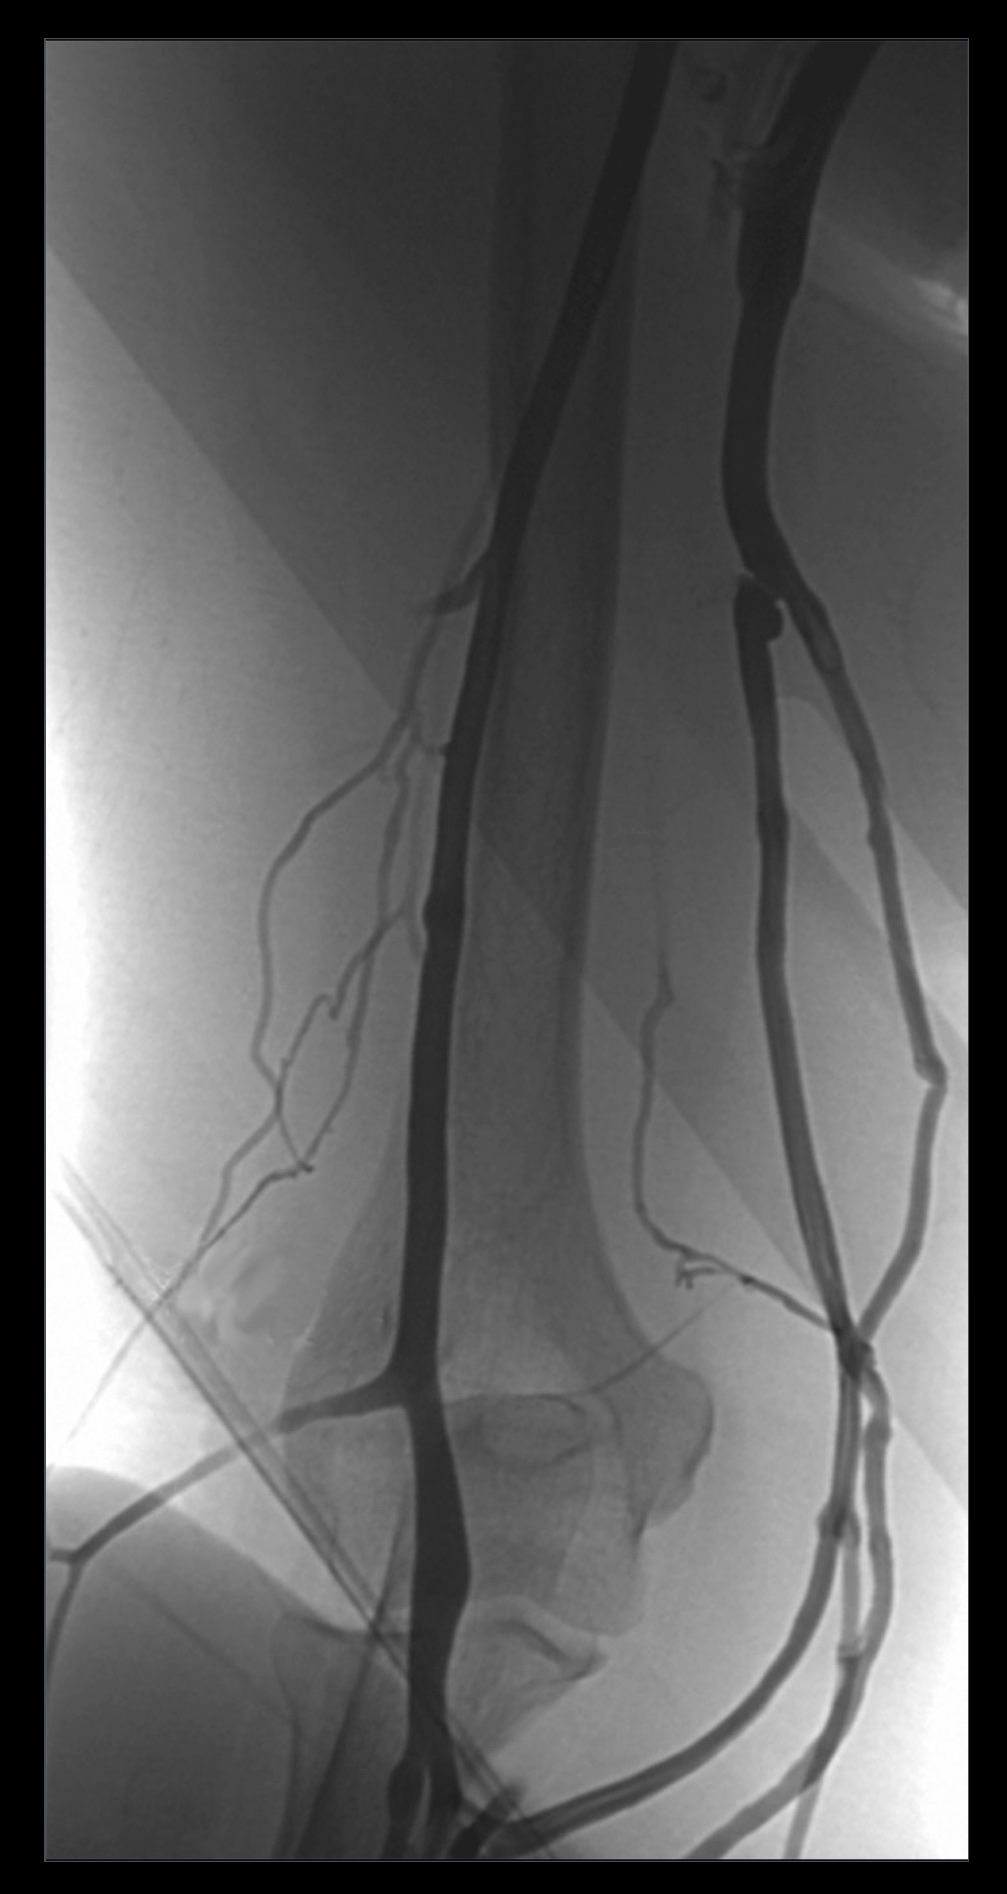

1. A patient complains of shoulder pain and difficulty rotating their arm. An ultrasound reveals edema within the spinoglenoid notch, which could explain weakness in external rotation at the glenohumeral joint. Describe the normal scapular and shoulder anastomosis, including all arterial branches involved and their relationship to any ligaments, scapula borders, and intermuscular spaces. If the axillary a. is ligated immediately distal to the thyrocervical trunk, would this edema affect active collateral circulation? (If yes, explain.) Also, include a brief (2-3 sentences) explanation for why edema within the spinoglenoid notch might result in weak external/lateral rotation of the shoulder.

4. The shoulder anastomosis provides adequate blood supply to the upper extremity during acute ligation of the axillary artery proximal to the subscapular artery. (False)

5. The scapular anastomosis provides adequate blood supply to the upper extremity during acute ligation of the axillary artery proximal to the subscapular artery. (True)

7. Acute axillary artery ligation proximal to the subscapular artery causes retrograde blood flow in the circumflex scapular artery. (True)